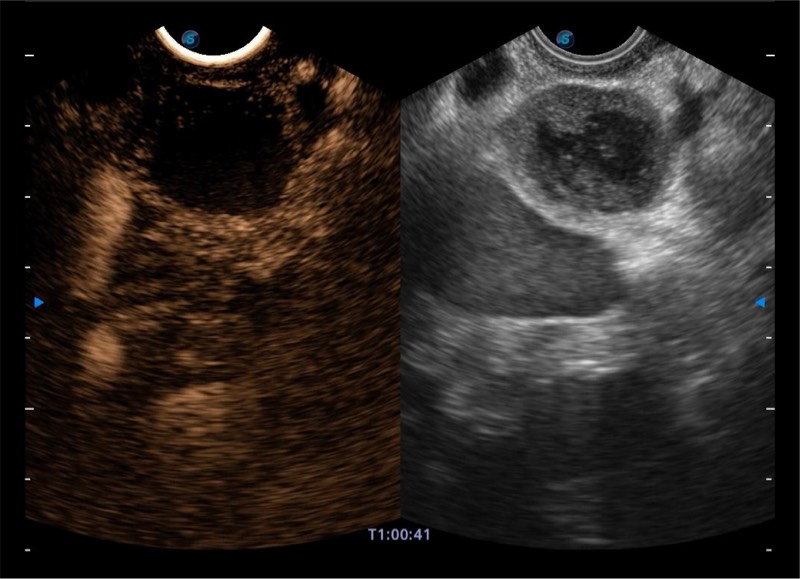

基于二十年的超声技术积累,银河集团官网提供了最新一代的独立超声主机,在提供高质量图像的同时满足多学科使用。具备常见多普勒技术并提供弹性成像、声学造影等高端影像技术。新一代传感器具有更强的抗干扰能力并减少图像伪影。

4-12MHZ宽频输出